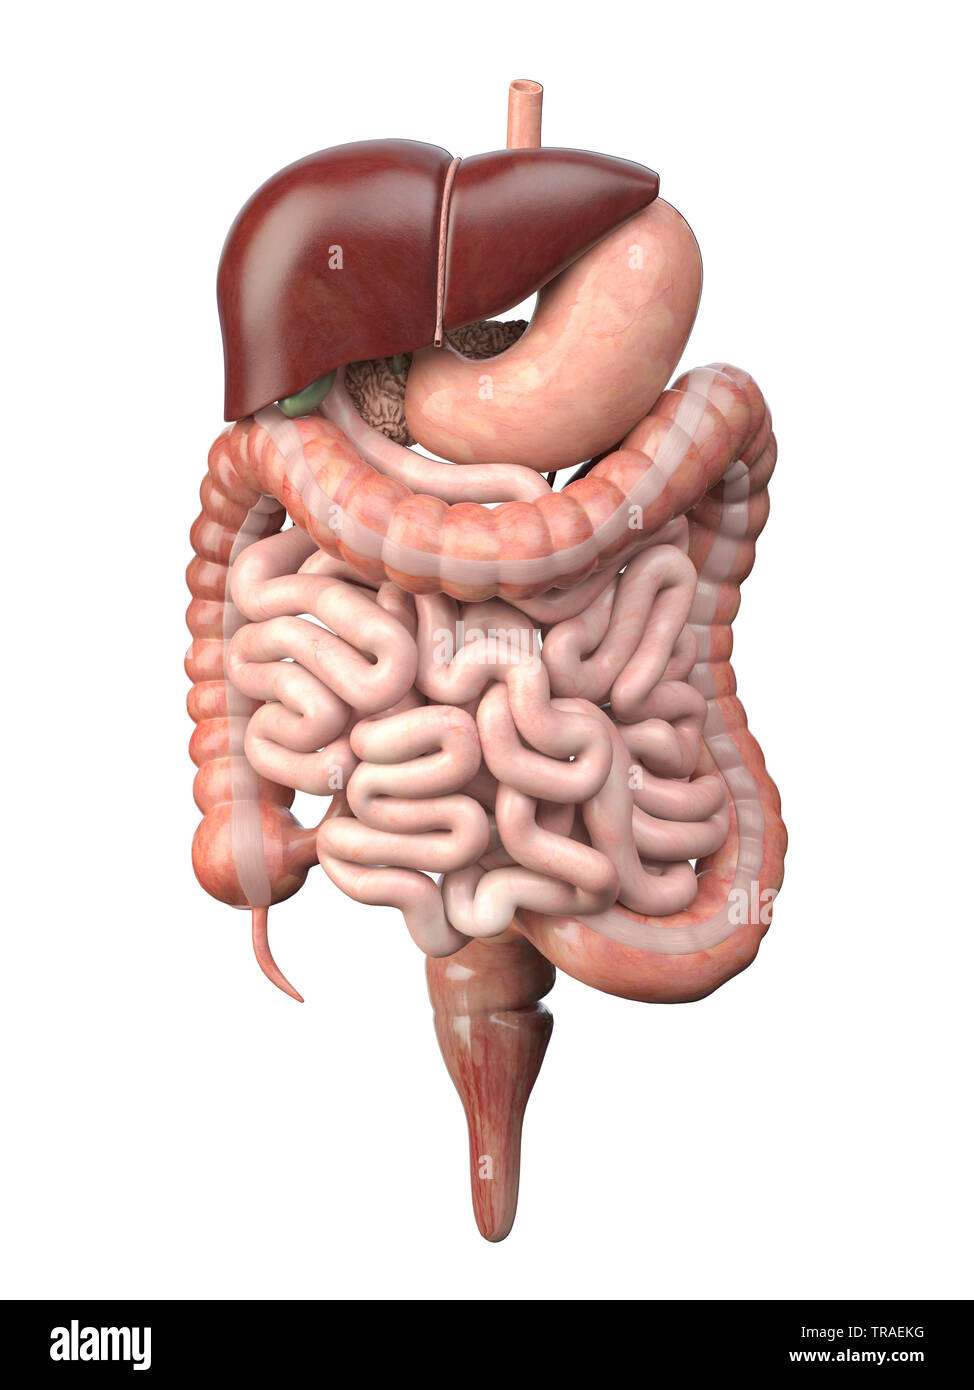

Изображения и визуализация внутренних органов человека

Раздел: Секреты мастерства